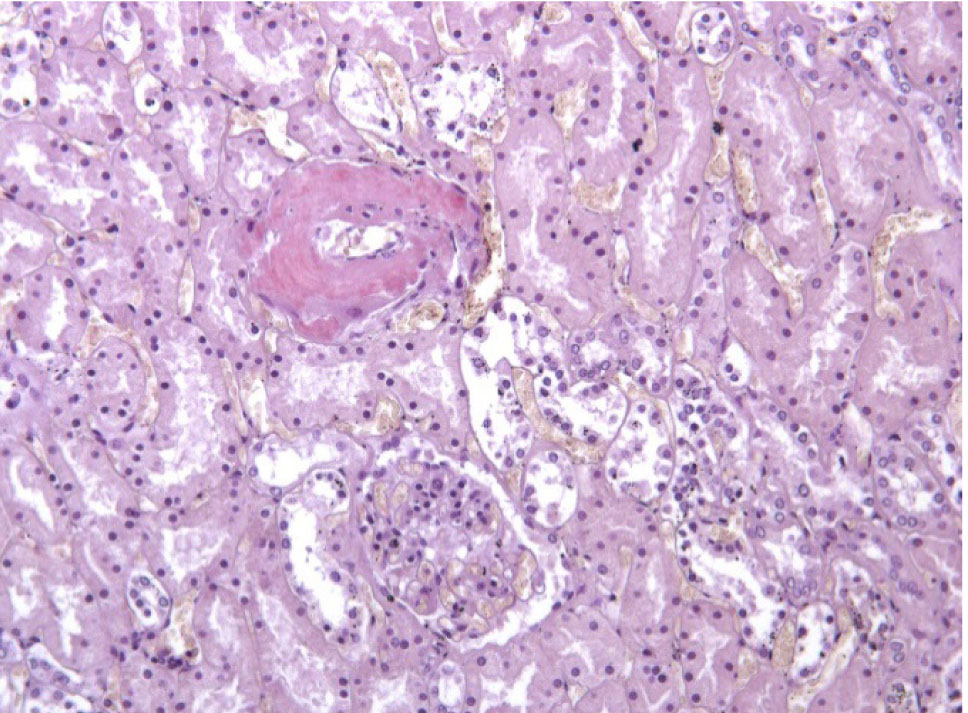

Почки – резкое уменьшение числа клубочков, отдельные полностью замещены однородной массой, дающей положительную реакцию на амилоид (рис. 3). В стенке сосудов также видны отложения амилоида (рис. 4).

Рис. 4. Амилоид в стенке сосуда в почке. Окраска конго красный, ×200